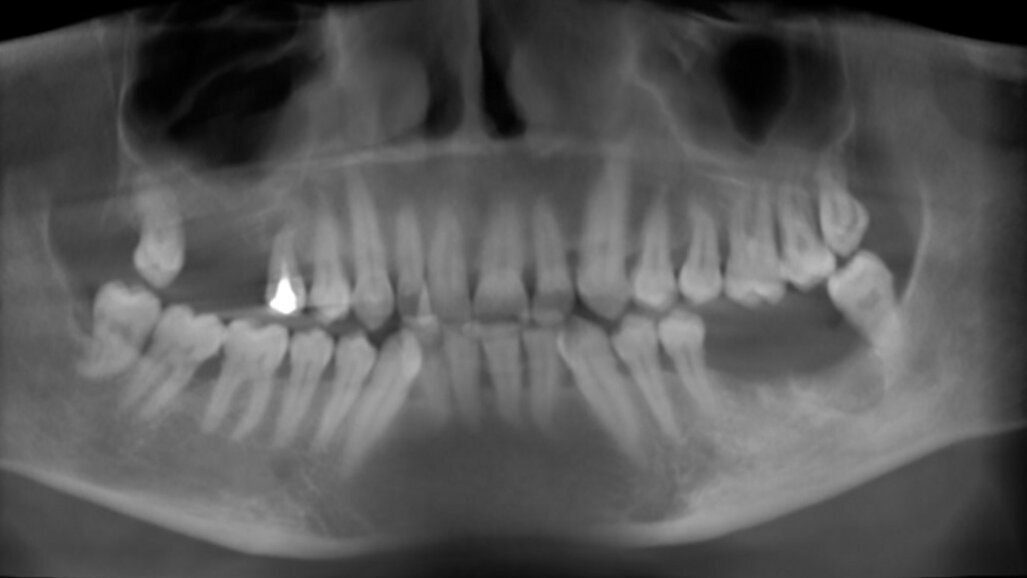

Una paziente donna di 63 anni, con osteoporosi ed ipotiroidismo, si presenta con assenza del 16 e 17, richiedendo riabilitazione dentale fissa. Si procede con l’esecuzione della CBCT per avere dettagli maggiori. Dall’analisi della CBCT nell’area edentula si misura un’altezza ossea verticale <5 mm in zona 16-17 e si nota la presenza di una lesione periapicale dell’elemento dentale 15 (Figg. 1-3). Quindi si programma l’intervento per l’estrazione del 15 e l’intervento per l’esecuzione del rialzo del seno mascellare con approccio laterale, con uso di osso bovino collagenato e spugnette di fibrina, al fine di ottenere l’incremento di osso verticale6. Dopo 5 mesi dall’esecuzione del rialzo di seno mascellare si esegue CBCT di controllo, per verificare l’effettivo aumento di osso verticale e programmare l’inserimento implantare (Figg. 4, 5).